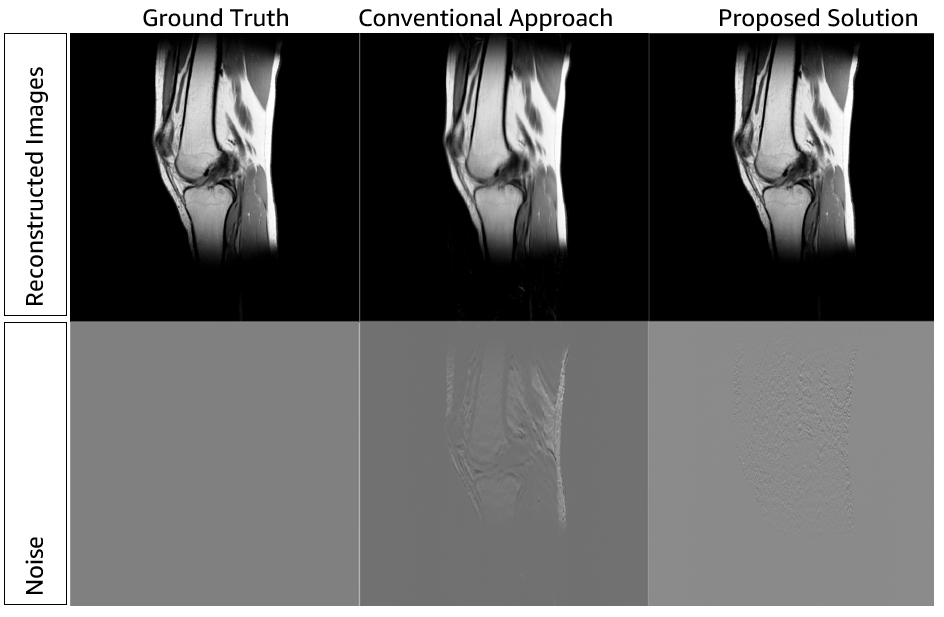

The application of the preceding architecture to a reconstruction job can yield the results in the following figure.

The image shows that good results can be obtained via reconstruction techniques such as RAKI. Moreover, adopting cloud technology can make these computation-heavy approaches available without the limitations found in on-premises solutions where storage and computational resources are always limited.